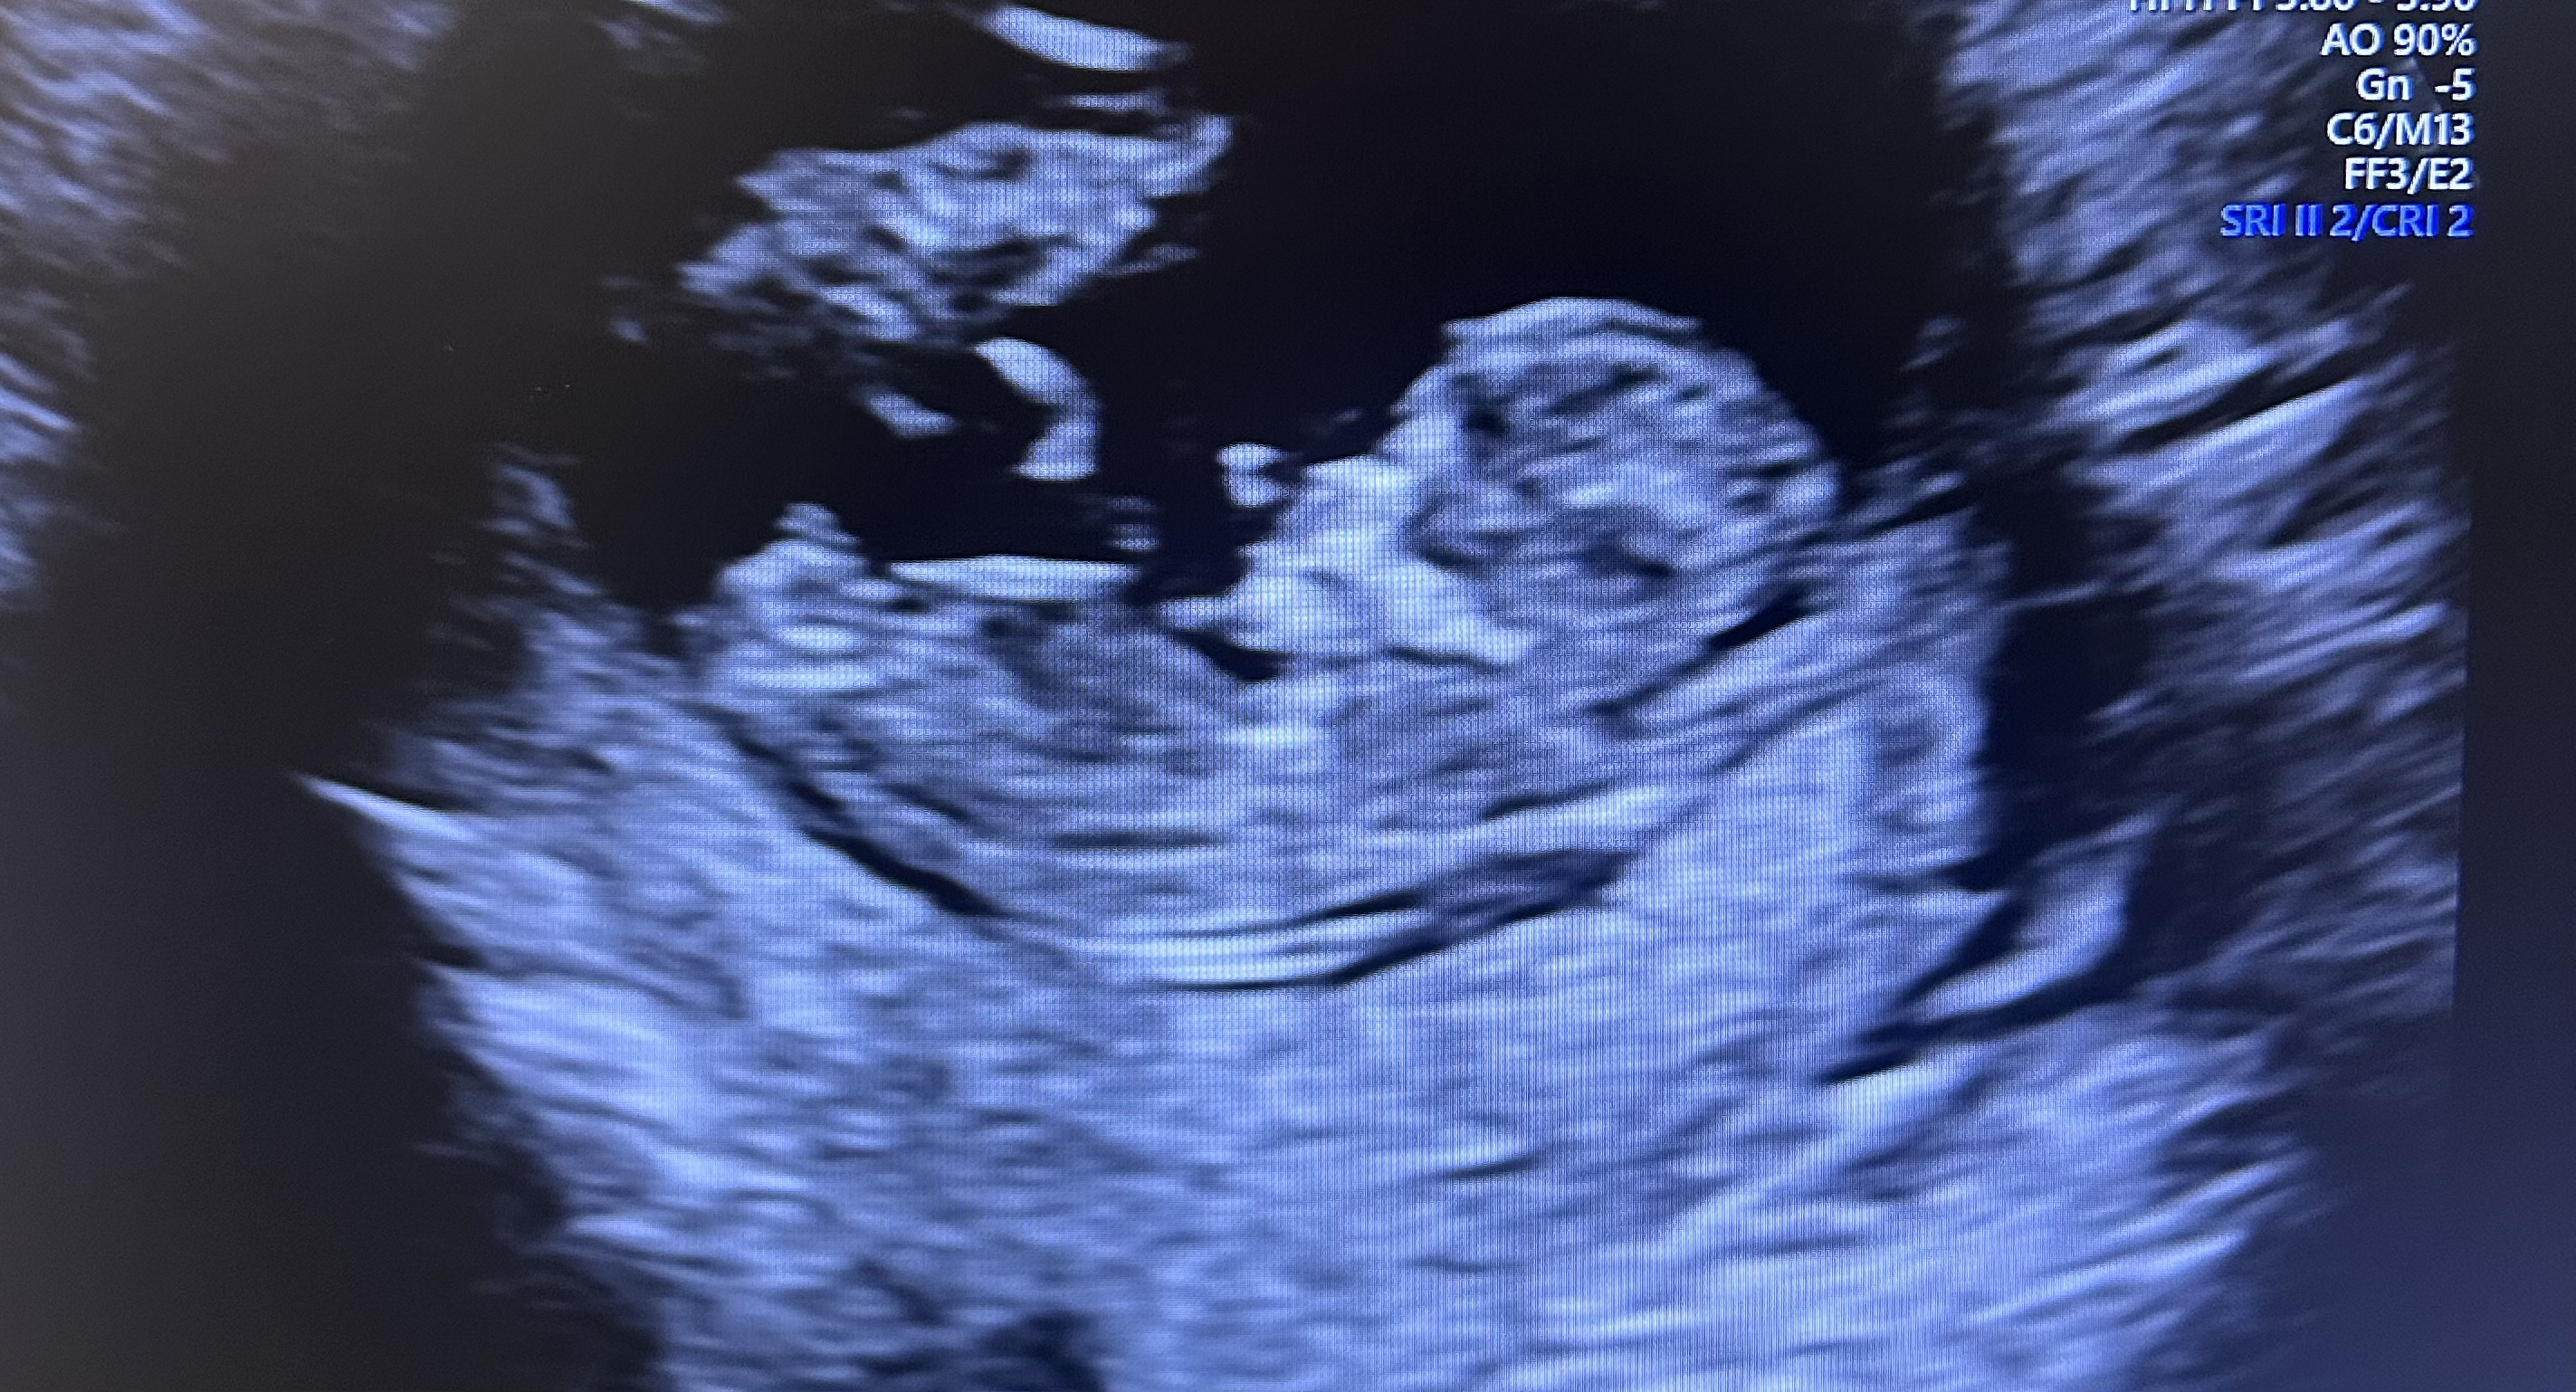

Первый скрининг близняшек

Анализы, скринингиВот и дождались первого скрининга. Кровь пока ждем, по УЗИ все отлично, патологий нет.

КТР 58 / 53 мм

БПР 18 / 17 мм

окружности головы 65 / 61 мм

окружности животиков 56 / 50 мм

ТВП 1.67 / 1.64 мм

носовые косточки визуализируются

PI 0.85 / 1.04

шейка 43 мм

фоточка только одного есть, второй прятался 🥹